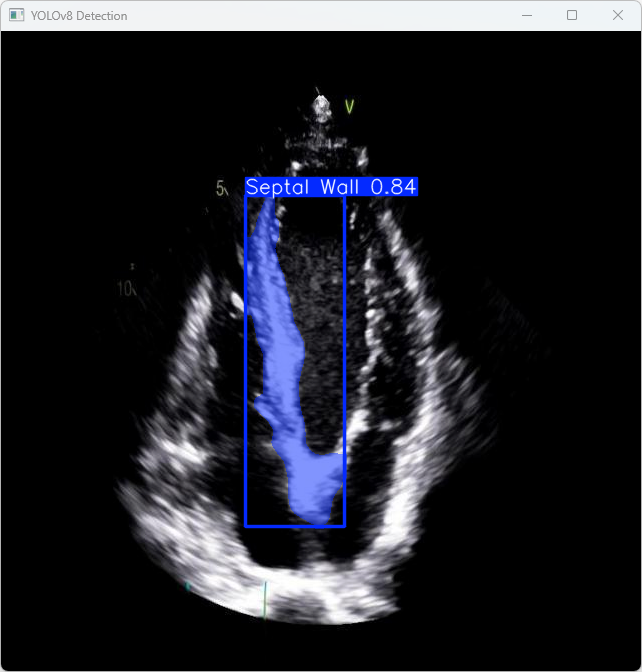

执行imgTest.py代码后,会将执行的结果直接标注在图片上,结果如下:

这段输出是基于YOLOv8模型对图片“benign (9).png”进行检测的结果,具体内容如下:

图像信息:

(1)处理的图像路径为:TestFiles/imagetest.jpg。

(2)图像尺寸为640×640像素。

检测结果:

(1)模型在图片中检测到:1个Septal Wall(心脏间隔壁)。

处理速度:

(1)预处理时间: 10.1 毫秒

(2)推理时间: 29.5 毫秒

(3)后处理时间: 110.3 毫秒

总结:

YOLOv8模型成功完成了对测试图像 imagetest.jpg 的心脏间隔壁检测和分割任务。模型在推理速度和精度方面表现不错。